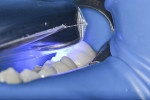

A conservative cavity preparation was performed to enable access to the affected dentin (Figure 6). After removal of the caries, both the enamel and dentin were etched (MAX Etch, Clinician’s Choice) for 20 seconds (Figure 7). The etchant agent was rinsed for 10 seconds (Figure 8) and lightly dried.

Although it was a small preparation with 2-mm depth into dentin, a desensitizing agent (G5) was used with a twofold purpose. The first reason was to desensitize the dentin because of the case involving a young patient with a large pulp chamber. The agent used desensitizes the dentin by coagulating the plasma proteins contained within the dentinal tubule fluid.16 The second reason was to stabilize the collagen fibers to prevent their degradation due to activation of MMPs.12,17 The desensitizer was applied with a microbrush for 10 seconds (Figure 9) and the excess removed, leaving a glistening appearance.